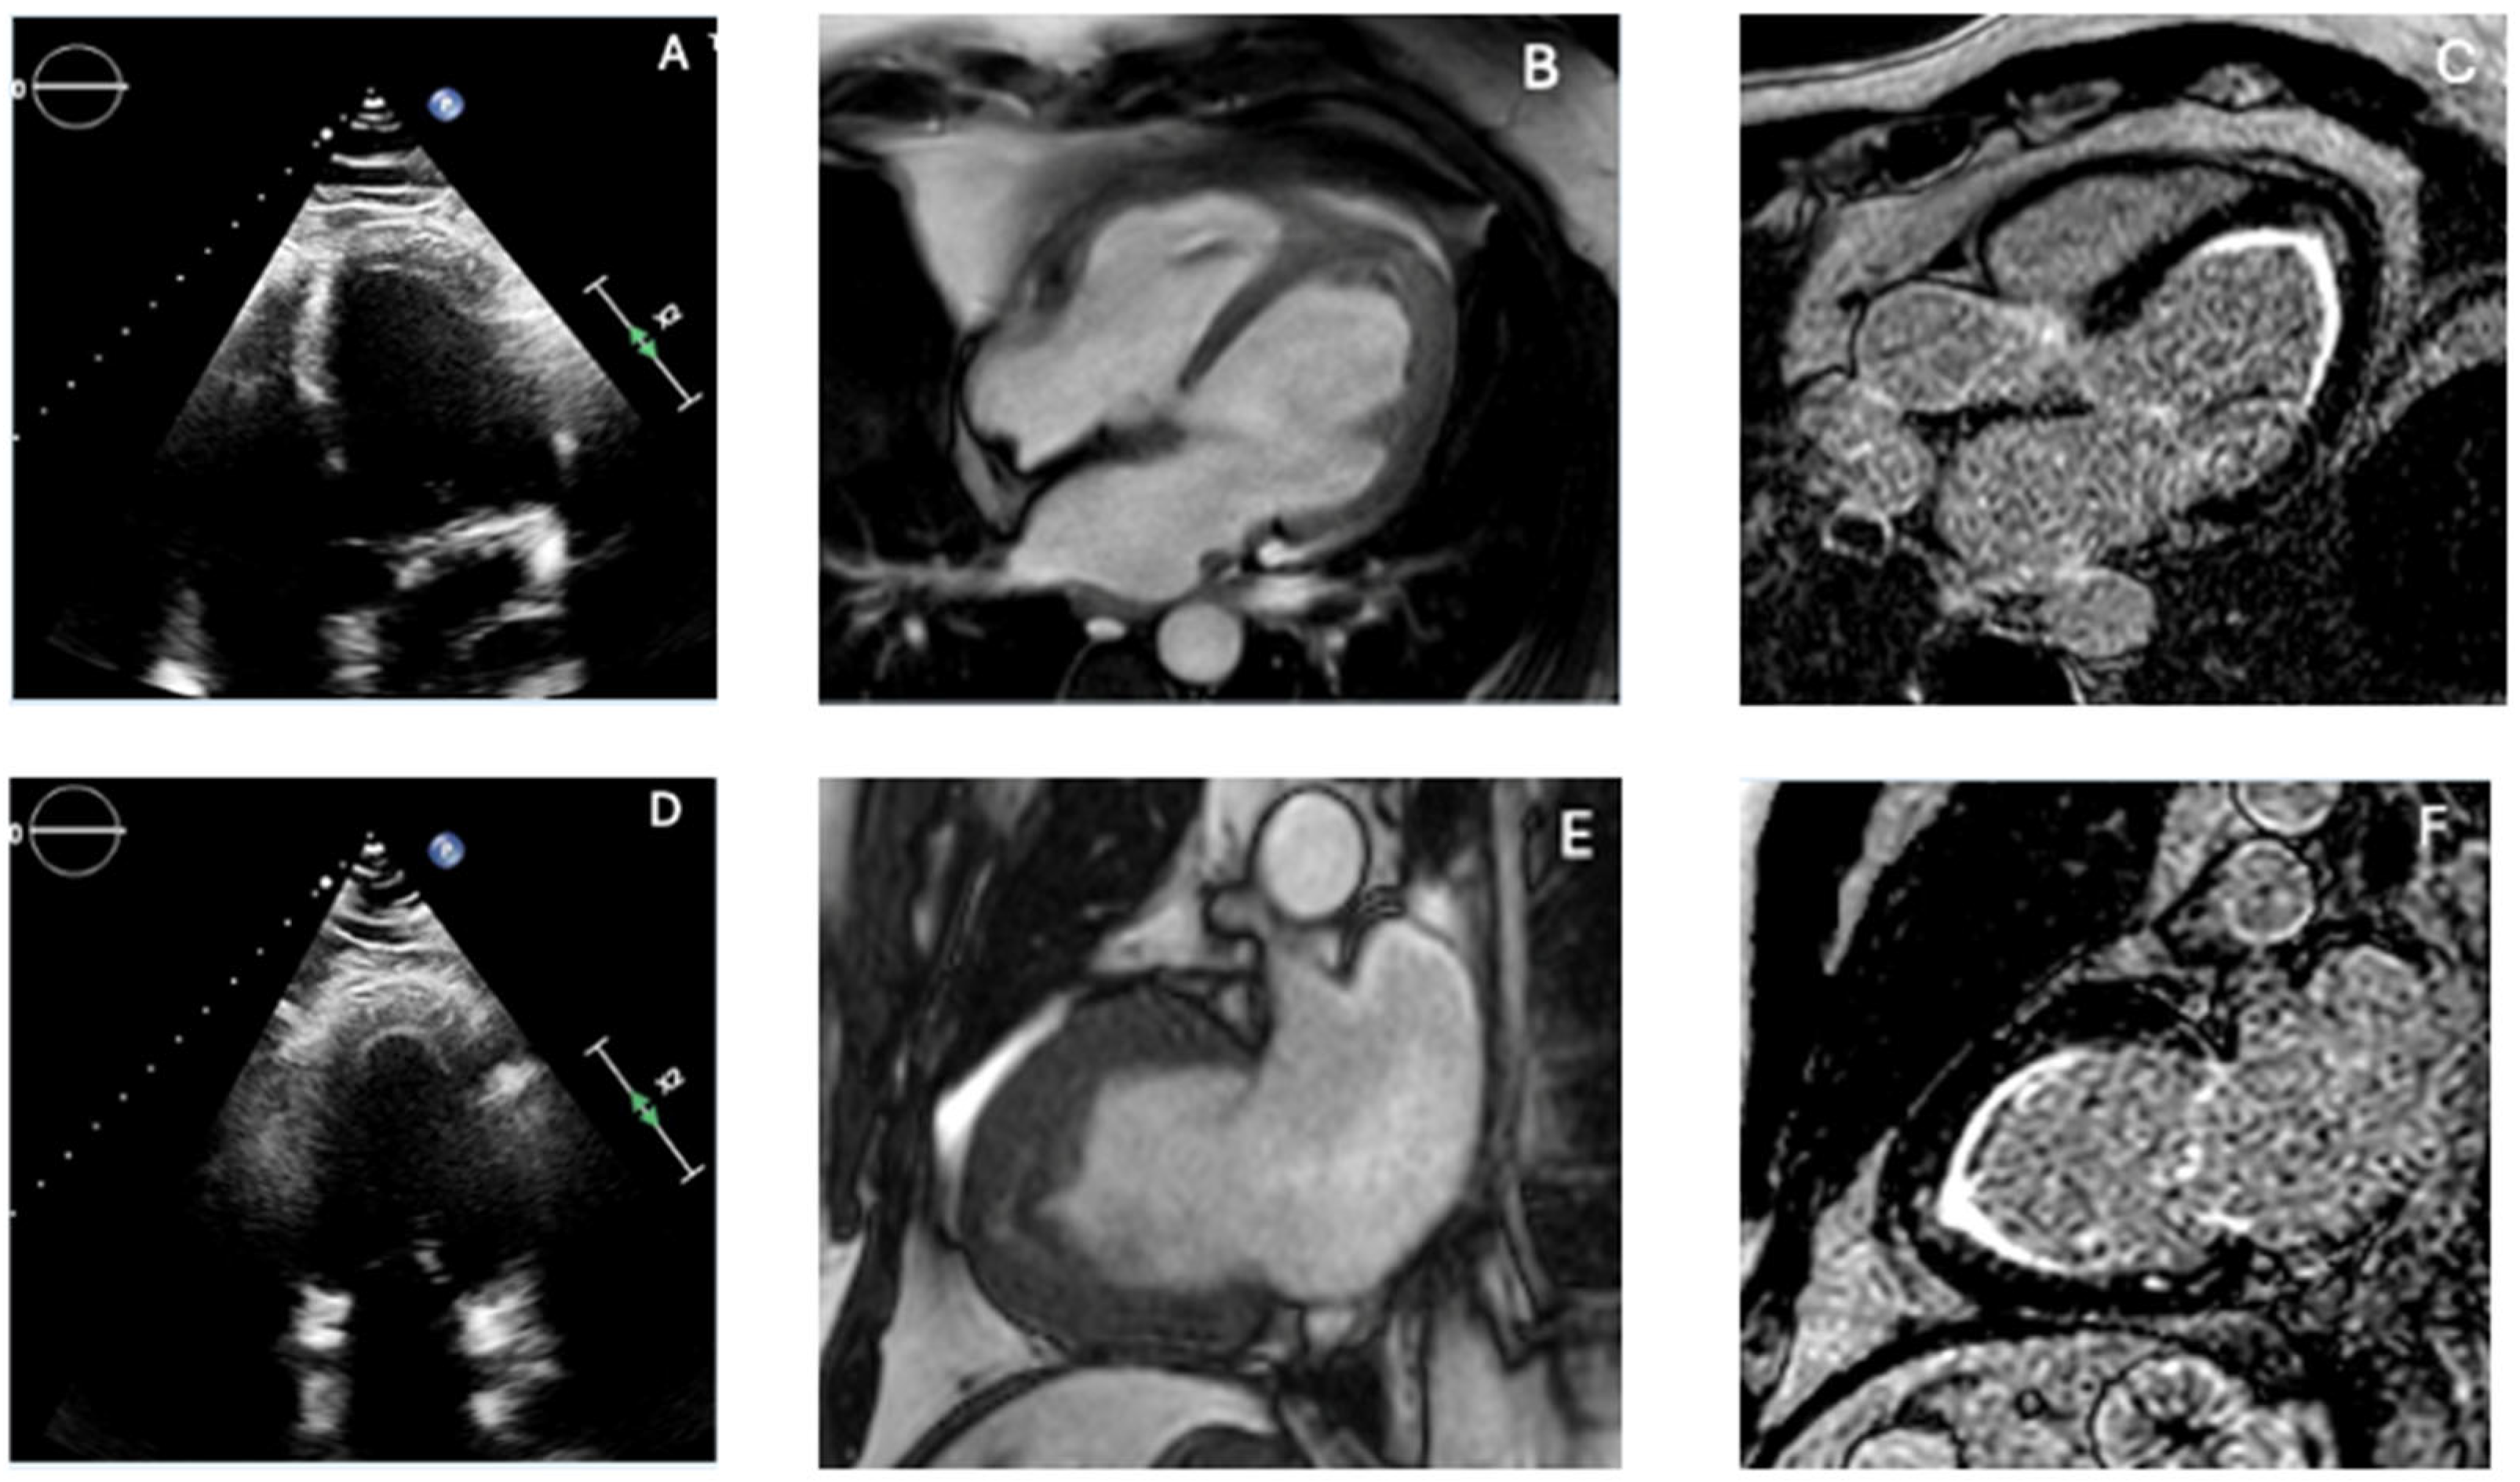

4.3. Left Ventricular Non-Compaction

| LV Noncompaction | Prominent trabeculations; deep recesses; ratio >2:1 | Regional strain heterogeneity | Hypertrabeculated apex; non-ischemic LGE possible | CT helps confirm anatomy |